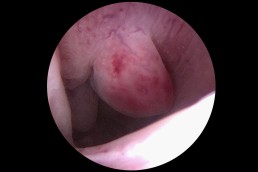

Polipii uterini reprezintă proliferări locale ale endometrului (mucoasa ce căptușește cavitatea uterină) și în marea majoritate a cazurilor sunt benigni. Ei pot provoca sângerări anormale, infertilitate sau pot interfera cu implantarea embrionilor în cursul fertilizării in vitro. Polipii endometriali pot fi diagnosticați cu ajutorul ecografiei, iar histeroscopia certifică acest diagnostic. În plus, histeroscopia permite și rezecția și extragerea polipilor endometriali. (fig. 3, 4)